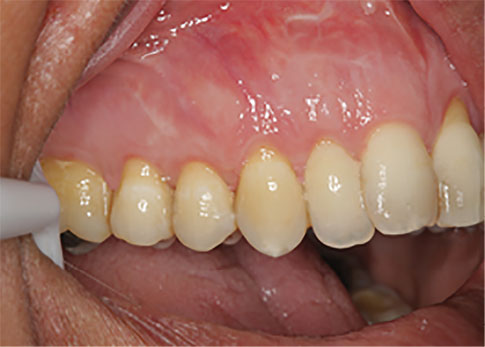

Figure 5.

Cenoderm site- 6 months after surgery.